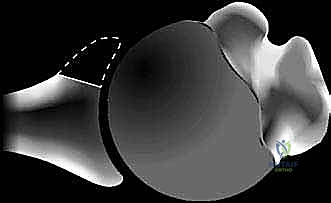

في الحالة الطبيعية، يكون الجزء السفلي من التجويف الحقاني أوسع من الجزء العلوي (شكل الكمثرى الطبيعي). ولكن مع تآكل العظم الأمامي السفلي، يفقد التجويف الحقاني عرضه في هذه المنطقة الحرجة. النتيجة هي أن الجزء العلوي يصبح أوسع من الجزء السفلي، مما يخلق شكل "الكمثرى المقلوبة".

الشكل 2 • يؤدي فقدان العظم الأمامي للتجويف الحقاني (الخط المتقطع في الصورة الأولى) بسبب التآكل أو الكسر إلى فقدان عرض التجويف الحقاني (A) وعمقه (B). والنتيجة هي شكل كمثرى مقلوبة لا يمكنه مقاومة إزاحة رأس العضد الأمامية بفعالية مثل التجويف الحقاني الطبيعي على شكل كمثرى.